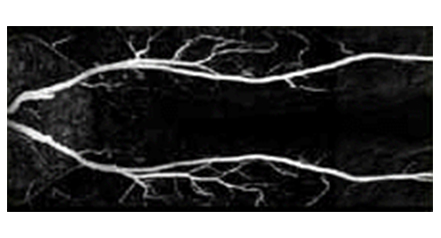

• 혈관 강조 영상(Magnetic Resonance Angiogram) 이미지

혈관 강조 영상

(Magnetic Resonance Angiogram)

특수한 영상기법을 이용하여 인체 내의 미세한 혈관까지도 묘출이 가능합니다.